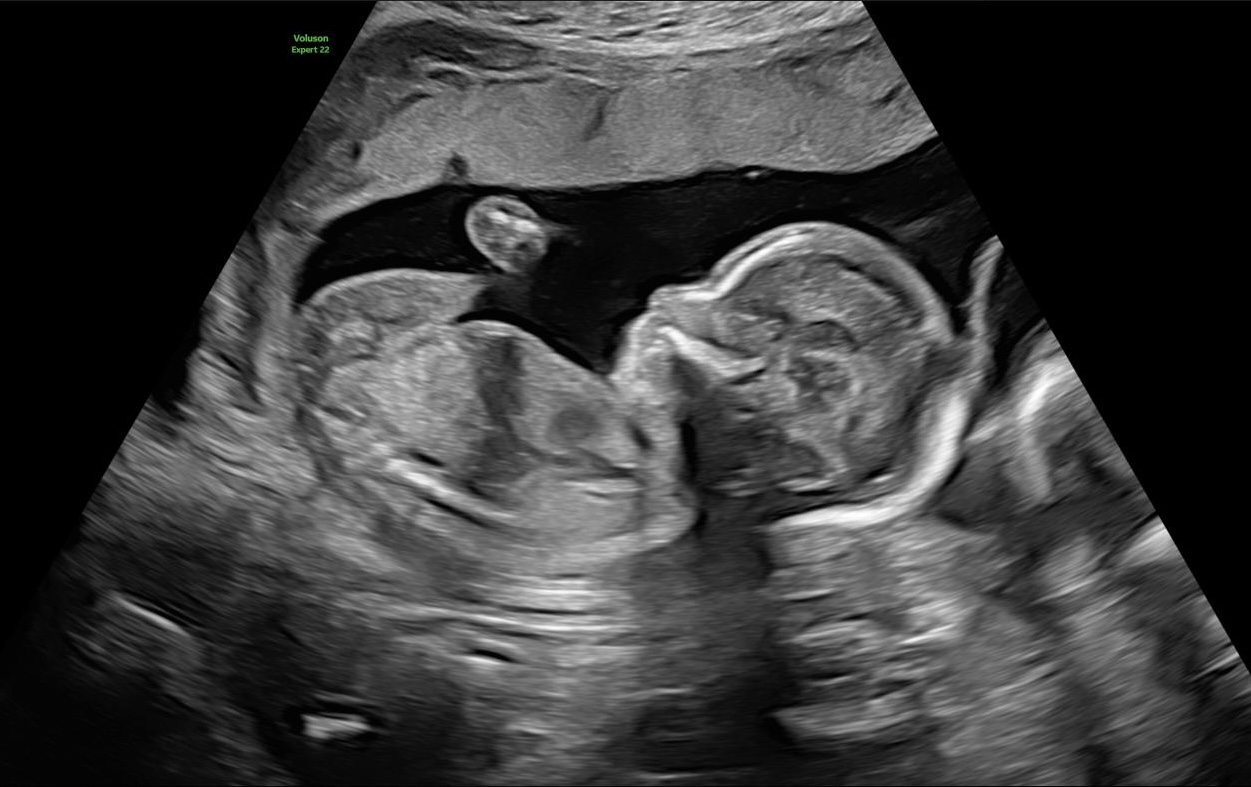

Gynekologiska och Obstetriska besvär inklusive 3D/4D ultraljud

3D/4D gynekologiska och obstetriska ultraljud